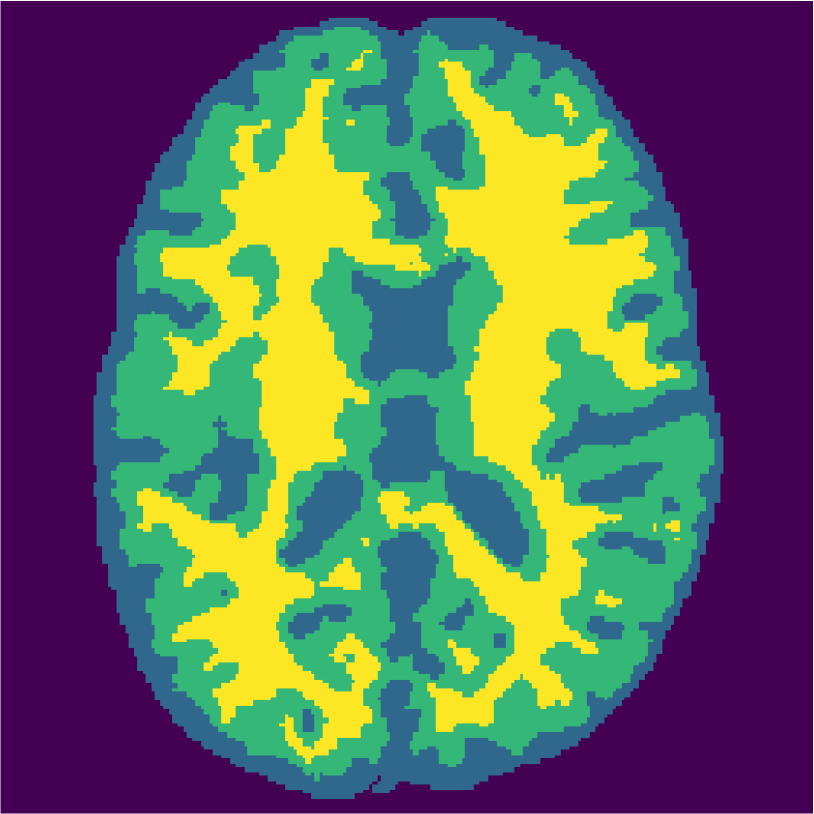

Examples of the segmentation results on one of the target test images are shown in Figure 8 for experiment 2.1, Figure 9 for experiment 2.2, and Figure 10 for experiment 2.3. Examples are shown after using 1 target patch per tissue for training, and after using 100 target patches per tissue for training. The results show that only the mrai-net classifier is able to predict a segmentation that approaches the ground truth with only 1 target patch per tissue for training (error for experiment 2.1 = 0.269, experiment 2.2 = 0.403, experiment 2.3 = 0.320), while the source and target classifiers cannot (source error for experiment 2.1 = 0.667, experiment 2.2 = 0.653, experiment 2.3 = 0.435; target error for experiment 2.1: 0.591, experiment 2.2: 0.614, experiment 2.3 = 0.596). After using 100 patches the source and target classifiers can predict a gross segmentation of WM, GM and CSF (source error for experiment 2.1 = 0.213, experiment 2.2 = 0.384, experiment 2.3 = 0.363; target error for experiment 2.1: 0.205, experiment 2.2: 0.368, experiment 2.3 = 0.368), but the mrai-net classifier prediction shows more details and a lower tissue classification error (error for experiment 2.1 = 0.111, experiment 2.2 = 0.276, experiment 2.3 = 0.284).